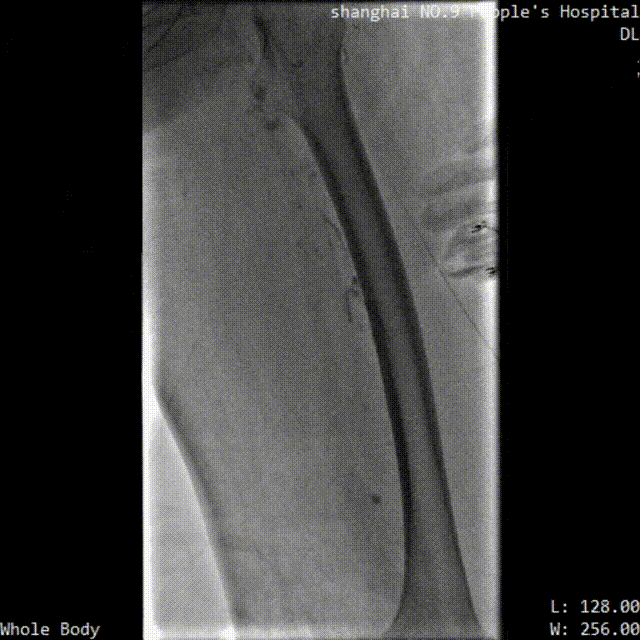

■ LuVoCaptor取栓前后管腔造影对照:

取栓术前管腔造影

取栓术后管腔造影

患者仰卧位,穿刺膝右侧股总静脉,造影定位下腔静脉,肾静脉位置,放置可回收腔静脉滤器;穿刺左侧腘静脉,置入导鞘,使用LuVoCaptor取栓导管作用靶病变,实施取栓后,即刻造影检查示血栓清除率>90%。导丝导管配合通过左髂静脉狭窄闭塞段返回真腔,后行球囊扩张术,再植入Wallstent支架。再次造影见左股浅静脉、股静脉、髂静脉、腔静脉、滤器内连续显影,未见明显充盈缺损,管壁形态血流速度快,造影剂无外渗。